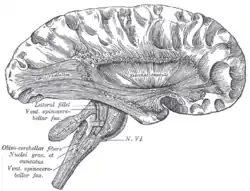

![]() Deep dissection of cortex and brain-stem. (External capsule visible at center.) | |

The external capsule is a series of white matter fiber tracts in the brain. These fibers run between the most lateral (toward the side of the head) segment of the lentiform nucleus (more specifically the putamen) and the claustrum.

The putamen separates the external capsule from the internal capsule medially and the claustrum separates it from the extreme capsule laterally. But the external capsule eventually joins the internal capsule around the lentiform nucleus.